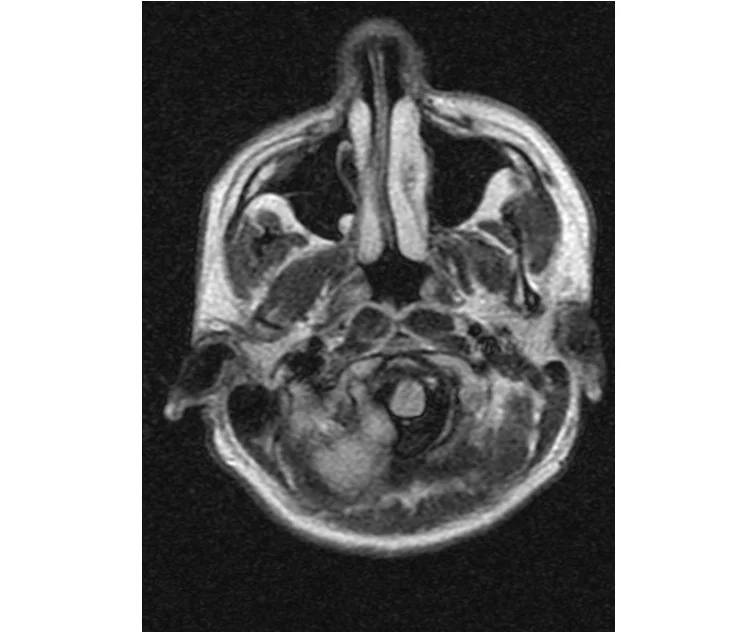

глянте на снимки томографии плиз

делал в обласной на siemense.В заключении выданом мне через 15мин.после мрт (легкая дегидрация)

Меня смутил факт выдачи заключения через 10мин(наверно они у них зарание напечатаные)я не медик.достаточно мимолётного взгляда на снимки?А вы видете на них гидроцефалию? Я лиш спросил куда идти с результатами томографии?и не хотел никого роздражать.

Я попросил взглянуть на снимки и сказать видна.ли на них гидроцефалия?или куда обратится за консультацией по этому вопросу?В мрт снимках наверно розбирается любой нервопатолог(я так предположил)

Я уже говорил, что независимо от того, есть на МРТ гидроцефалия или нет, лечиться тебе нужно только в том случае, если есть какие-либо проявления болезни, иначе на все эти анализы можешь забить... Но давай все-таки разберемся с томограммой.